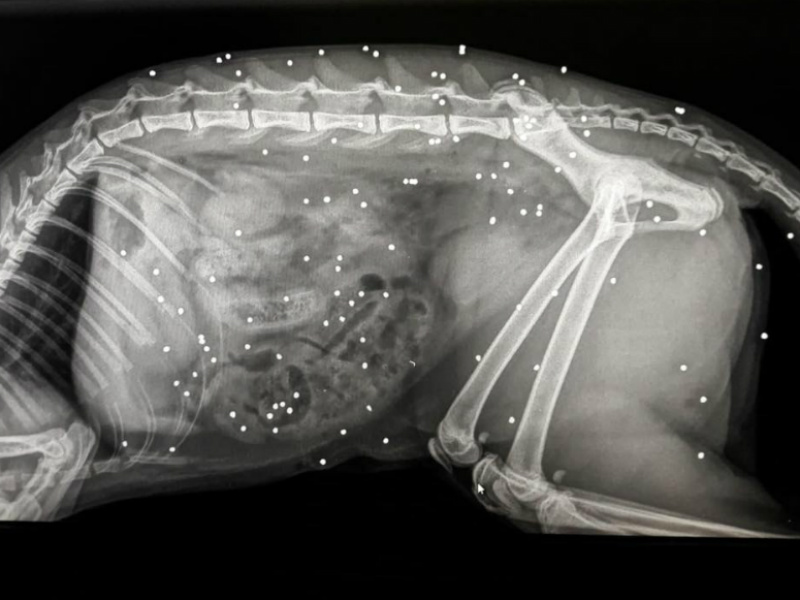

Foto Notizia: Micia impallinata più di settanta volte

Crudeltà inaudita nei riguardi di una gatta che è stata impallinata oltre settanta volte da persone non ancora identificate. A salvare l’animale domestico sono state le cure dell’equipe staff della Clinica veterinaria Niccolò Copernico al Ciarnin che dopo aver rimesso in sesto la micia ha deciso di divulgare sui social la foto della lastra dove si possono notare i numerosi colpi ricevuti dall’animale.

“Questa povera micia è arrivata da noi in clinica in shock con un numero imprecisato di fori causati dai pallini ad espansione. Curata e assistita ora sta bene ed è tornata a casa. I proprietari hanno denunciato l’accaduto. Vorremmo non vedere mai animali sofferenti a causa della mano dell’uomo e non stupirci più di fronte a tanta stupidità e cattiveria. Purtroppo non è l’unico caso, ci è già capitato anche in passato spiega la dottoressa Gemma Mastronardi -. Abbiamo pubblicato questa foto proprio per sensibilizzare l’opinione pubblica perché è un gesto terribile”.